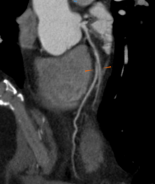

Chẩn đoán hình ảnh mô mềm tiên tiến cho vùng bụng.

Tăng cường độ tương phản I-ốt.

Hỗ trợ đánh giá an toàn cho bệnh nhân.

Đảm bảo hình ảnh chất lượng cao.